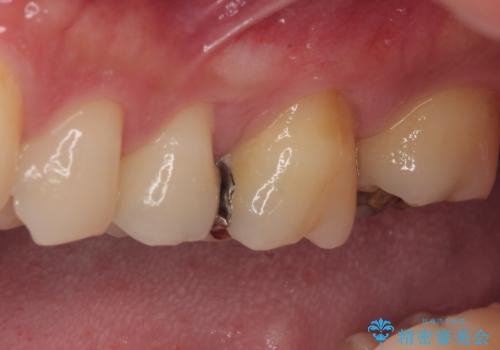

放置した欠損部 奥歯の即時荷重インプラント治療

- 左下欠損部のインプラント治療を希望して来院された患者様です。

左下の欠損部を長期間欠損を放置していたことで、咬み合う上の奥歯が動いてしまっている状態でした。

インプラント部は埋入とともに仮歯を装着し、同時に上顎奥歯の部分矯正を開始することとしました。

理想的な咬み合わせに改善した上で、インプラント補綴治療を行うこととしました。